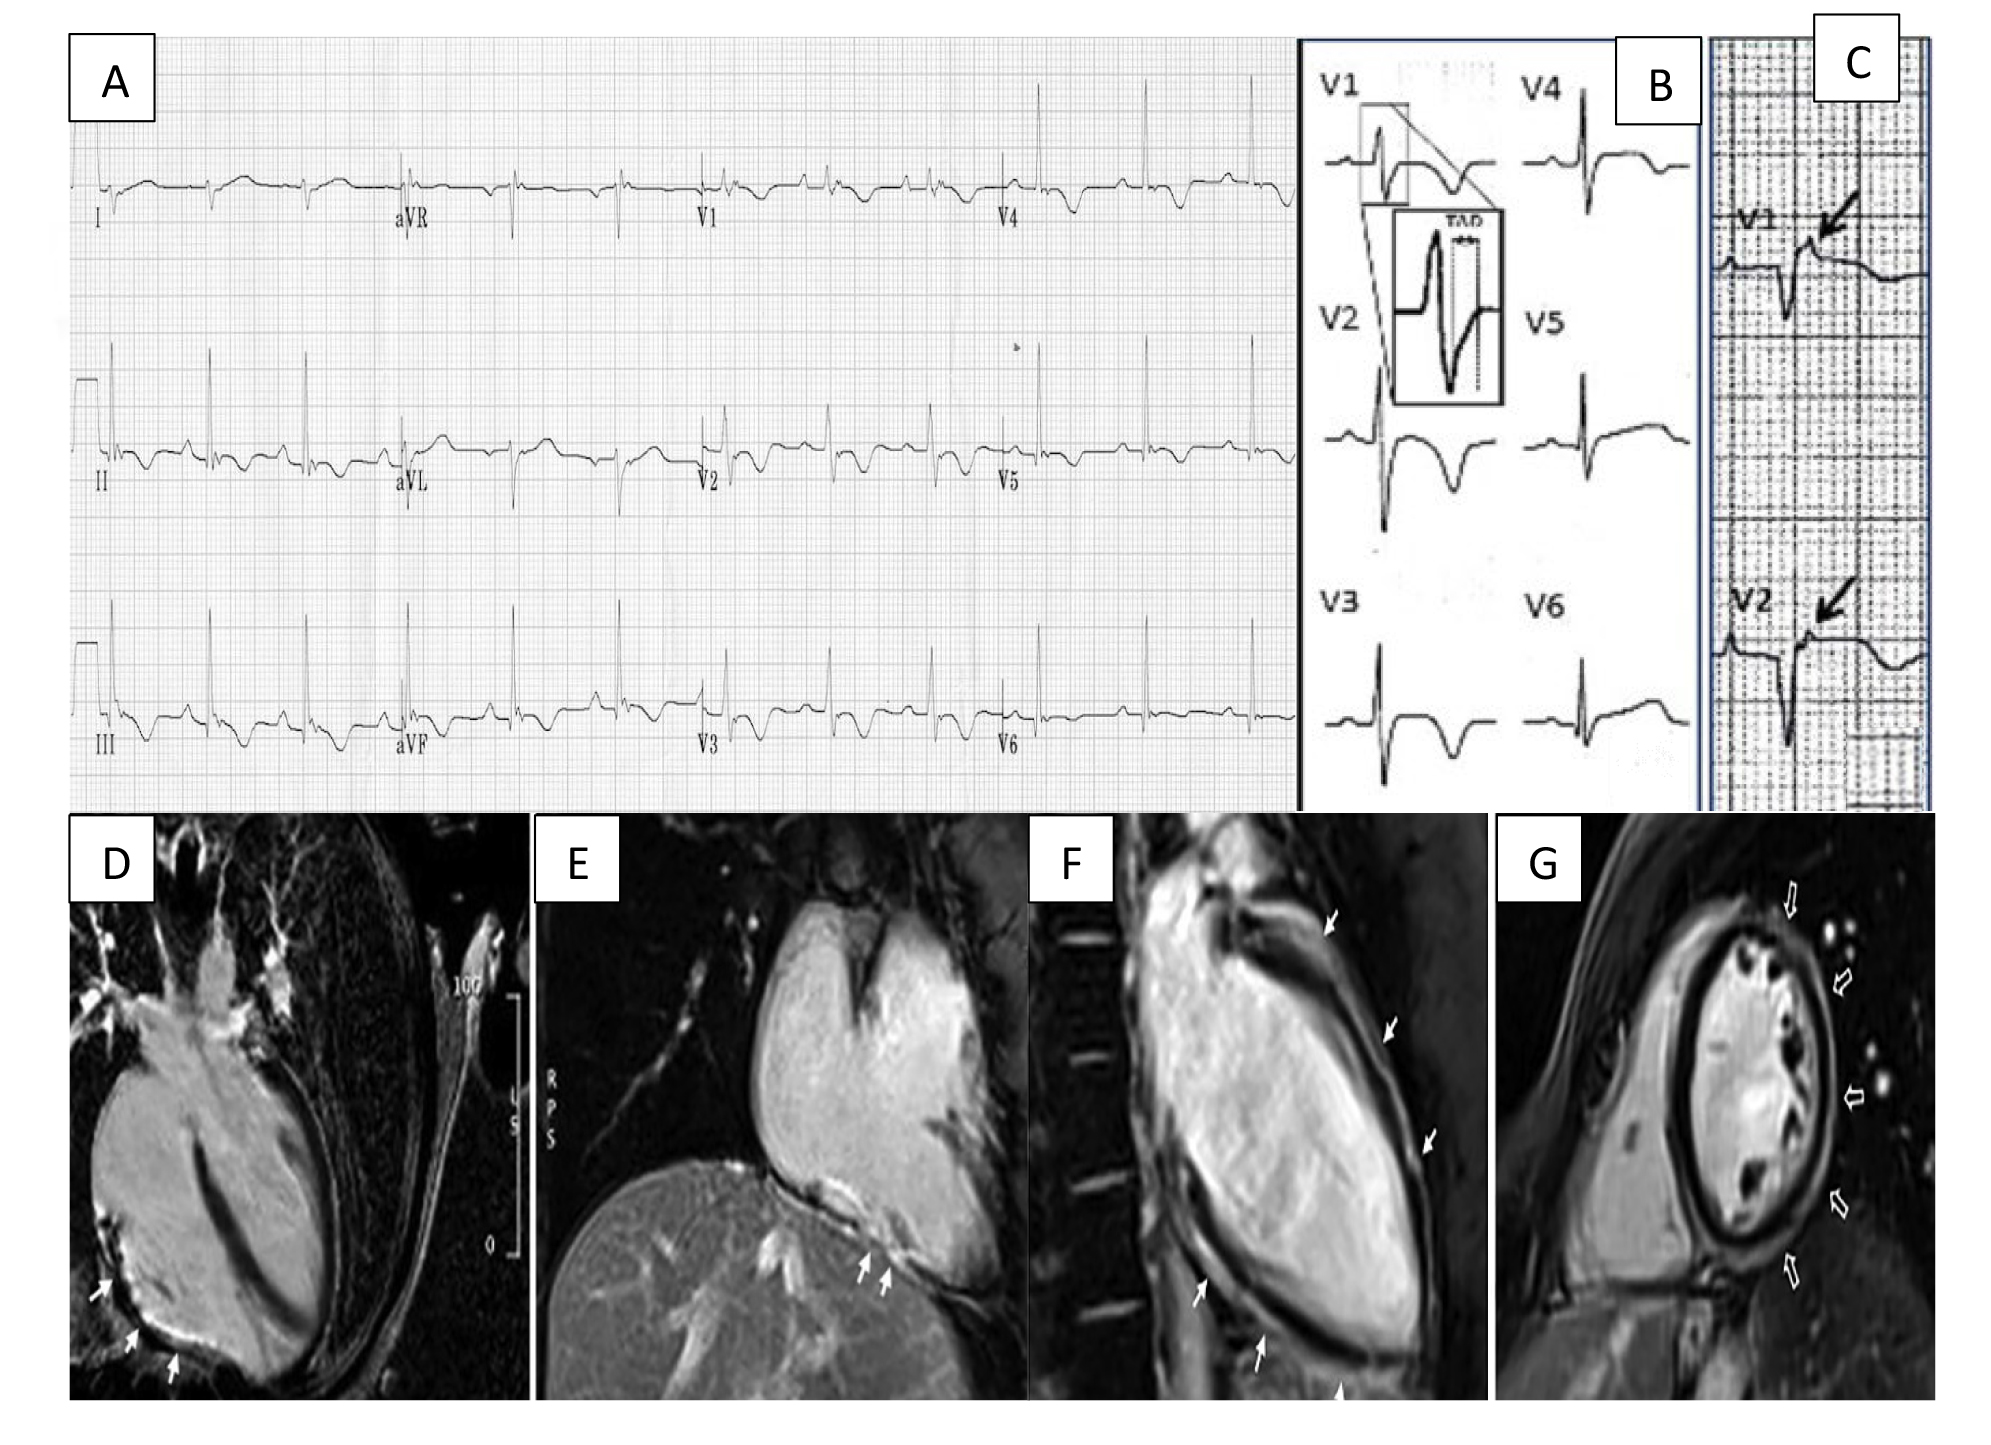

Understanding the electrophysiological perturbations implicated in ACM is essential for screening, diagnosis, risk stratification and guiding therapeutic interventions. The nature of structural changes within the myocardium modulates transmission of electrical signals and can result in conduction defects that may be visible on a standard 12-lead ECG (Fig. 1, Ref. [20]).

Fig. 1.Arrhythmogenic cardiomyopathy findings electrocardiogram (ECG) and CMR. (A) ECG focusing on the precordial leads with characteristic T wave inversion in leads V2–V5 and an epsilon wave in V1. (B) Widening of the QRS with classical T wave inversion in leads V2–V4. A close-up view of the delayed S upstroke within the QRS is also indicated. (C) Arrows highlighting epsilon wave in V1–V2. (D) A long axis 4 chamber view CMR showing LGE/fibrous replacement of RV diaphragmatic free wall (indicated by the arrows). (E) Sagittal view CMR emphasising the fibrous replacement of the RV anterolateral wall. (F) CMR depicting subepicardial LGE of the LV extending from the base to apex segment in the sagittal view. (G) CMR image showing a post-contrast ‘ringlike’ pattern in the short axis view. CMR, cardiac magnetic resonance imaging; LGE, late gadolinium enhancement; LV, left ventricle; RV, right ventricle. Figure adapted with permission from (1) ECG Library. Life in the Fast Lane. https://litfl.com/ecg-library/. Accessed March 26, 2023. (2) Corrado et al. Proposed diagnostic criteria for arrhythmogenic cardiomyopathy: European Task Force consensus report. International Journal of Cardiology. 2024 Jan; 395: 131447. [20]